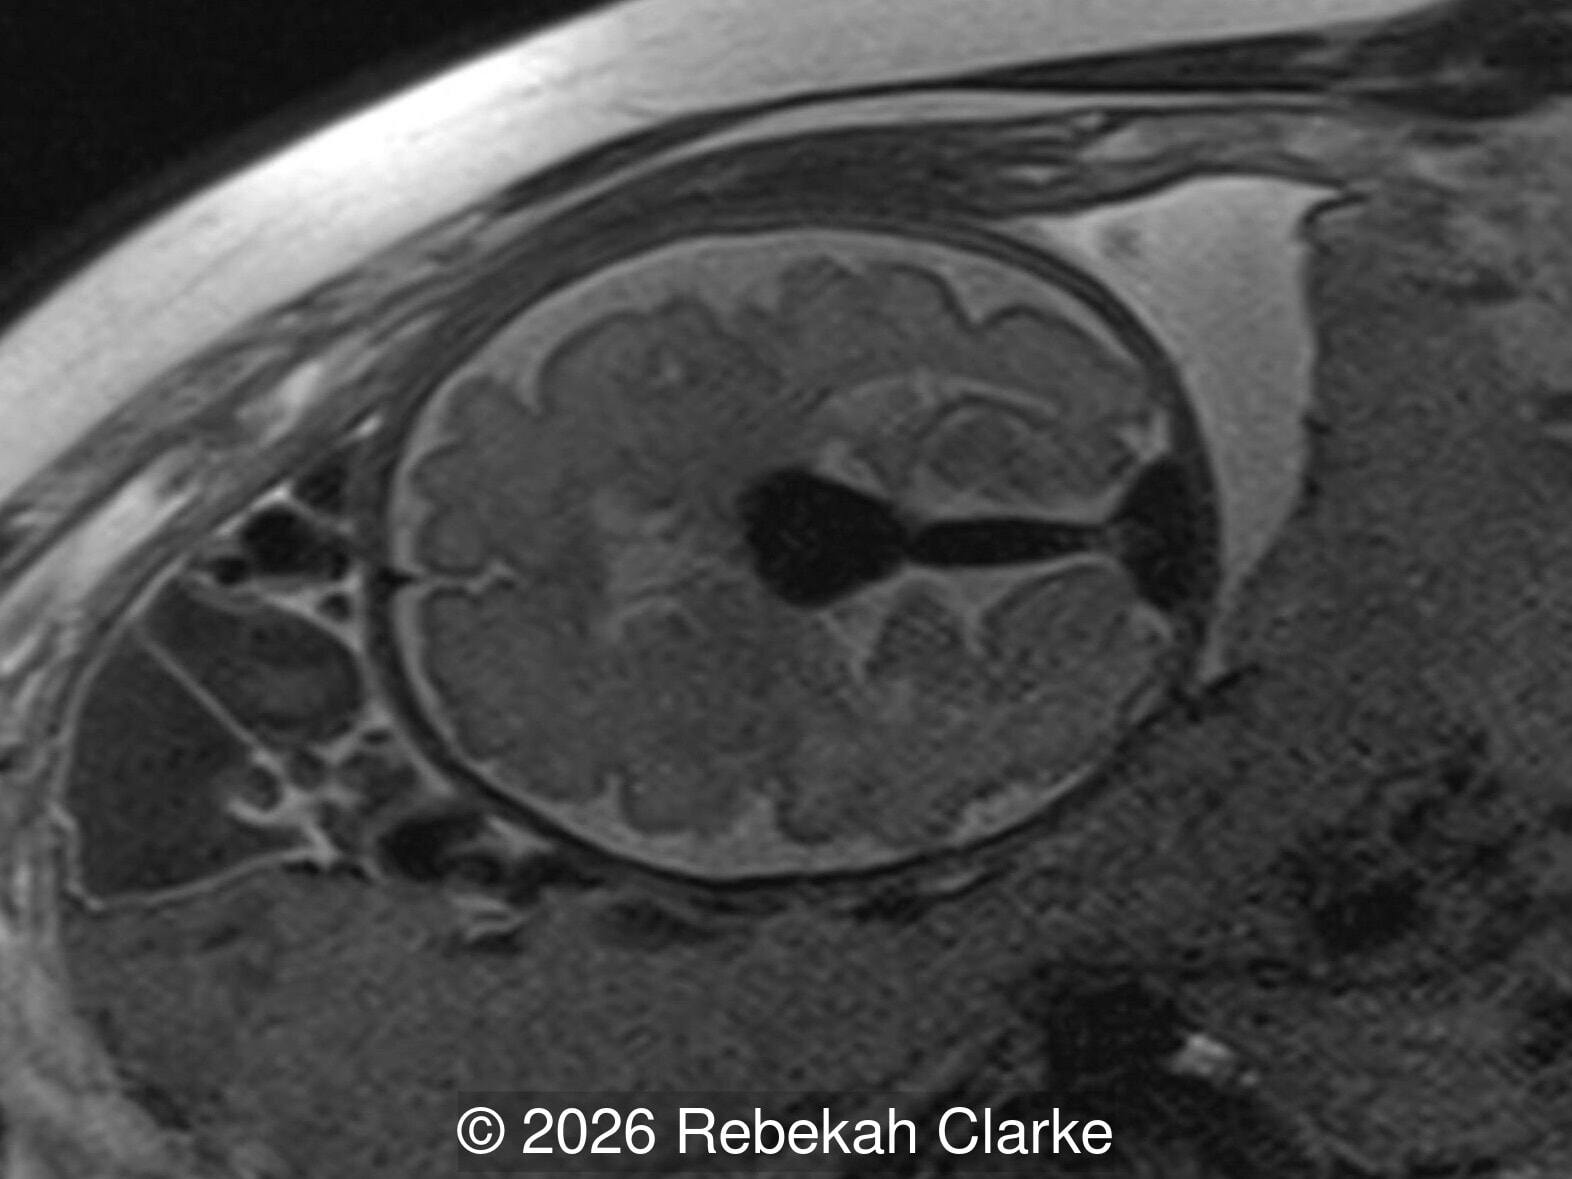

The diagnosis was confirmed by fetal magnetic resonance imaging (MRI). Our patient did not meet the criteria for in utero embolization. At 37 weeks she was delivered via cesarean section and underwent postnatal embolization.

Axial T2-weighted image through the fetal brain at the level of the cavum septum pellucidum, showing the prominent T2 hypointense flow void of the vein of Galen malformation.

Image 6 Axial T2-weighted image through the fetal brain at the level of the cavum septum pellucidum, showing the prominent T2 hypointense flow void of the vein of Galen malformation.

Sagittal T2-weighted image showing the large T2 hypointense flow void of the vein of Galen malformation.

Image 7 Sagittal T2-weighted image showing the large T2 hypointense flow void of the vein of Galen malformation.